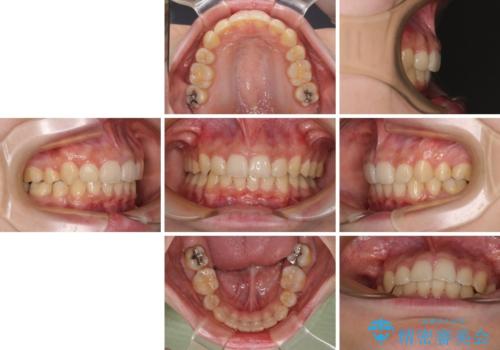

下顎前歯が隠れて突出した口元 ワイヤー装置での抜歯矯正

- 前歯のデコボコと口元の突出感を気にして来院された患者様です。

下顎骨の左右差や、上顎骨の前方位などが認められたため、上下左右の第1小臼歯4本を抜歯し、ワイヤー装置にて矯正治療を行うこととしました。

骨格的な左右差がありましたが、何とか当初予定していた期間で、左右対称の咬み合わせに仕上げることができました。